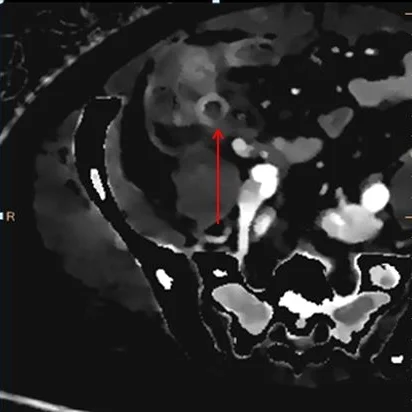

Iodine density image. Note focal discontinuity in appendix enhancement (red arrow). This is consistent with perforation.